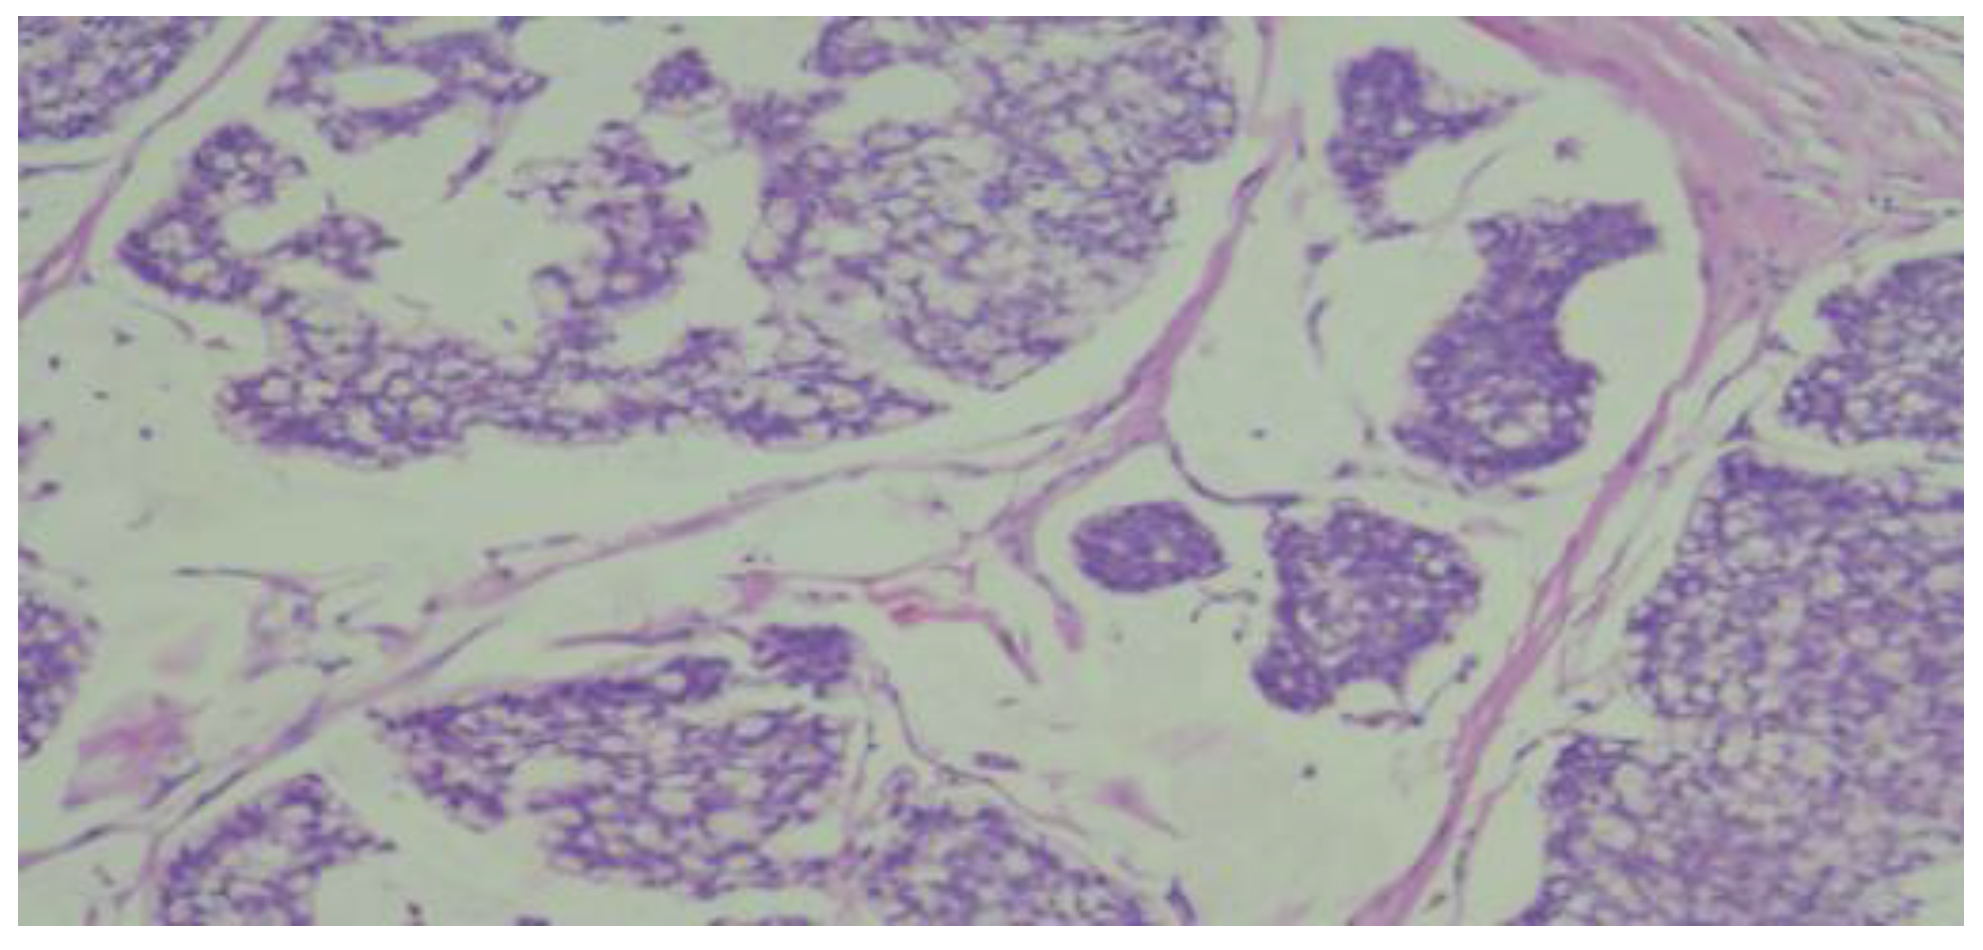

The pathological result identified macroscopically a tumor mass of 1.5x1.2 cm, situated 1 cm below the skin, 1.5 cm from the deep resection margin, and 9 cm, 7 cm, 8.5 cm, and 6 cm from the other resection margins. Multiple fragments measuring 5.5x5.2 cm in size, composed of adipose tissue containing lymph nodes, were also observed. The histopathological appearance corresponded to an invasive mixed mammary carcinoma – 70% mucinous carcinoma and non-specific invasive ductal carcinoma (Figure 4 and Figure 5), Nottingham grade II %E% (architectural grade = 3, nu-clear grade = 2, mitotic grade = 1), and tumor staging pT1cN0Mx. The diagnosis of mucinous carcinoma was based on histological characteristics, namely nests and groups of tumor cells forming within a mass of extracellular mucin.

Figure 4. Microphotograph smear examination showing invasive ductal carcinoma component.

Figure 5. Microphotograph smear from case has identified mixed (ductal and mucinous) carcinoma.

The NOS type ductal carcinoma component consists of nests and trabeculae of varying sizes arranged in a moderately connective stroma; the tumor cells are polygonal, slightly larger than those in the mucinous component, with no distinct cell boundaries, moderately eosinophilic cytoplasm, and euchromatic or vesicular nuclei, with small nucleoli (HE10X).

The mucinous carcinoma component is made up of medium-sized polygonal cells, with poorly and focally visible cell borders, with eosinophilic or pale cytoplasm, with clear intracytoplasmic vacuoles and a small euchrome nucleus, and some have the appearance of signet ring cells (HE20X).